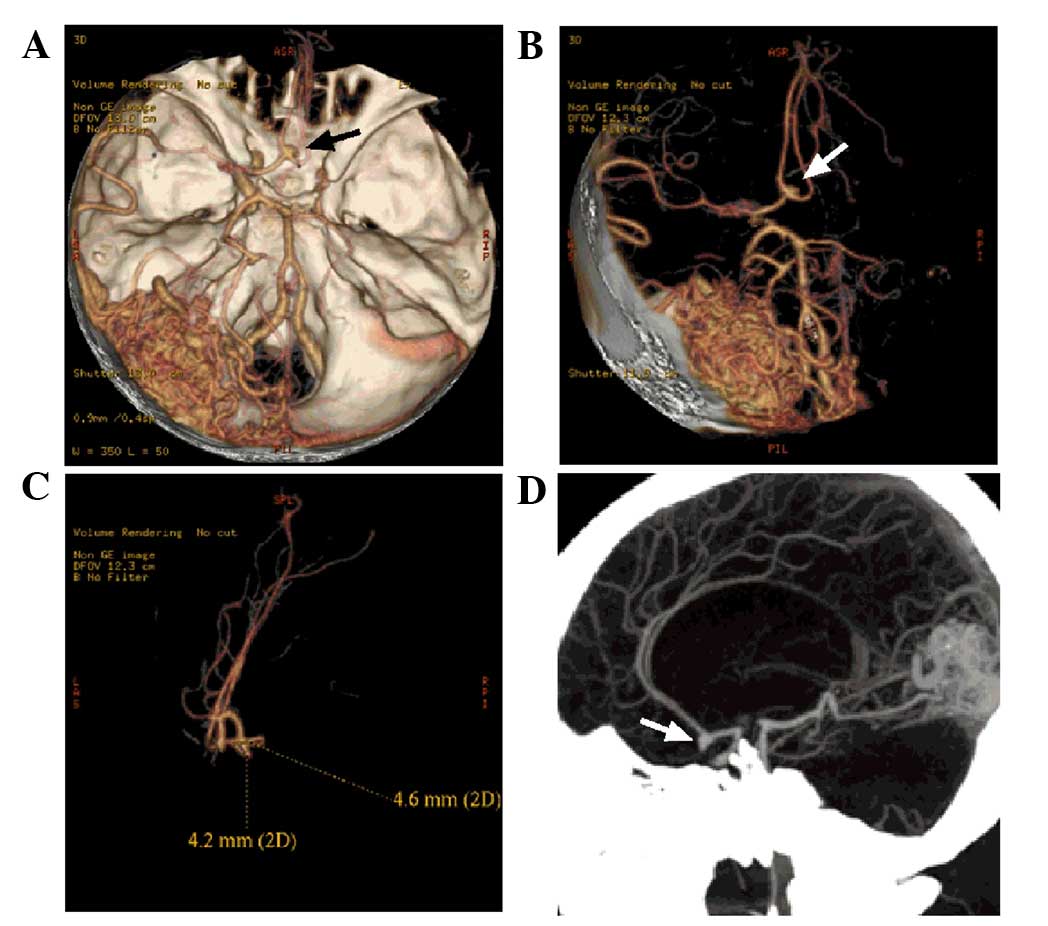

Following admission, a head computed tomography (CT) scan (SOMATOM Definition AS; Siemens AG, Munich, Germany) revealed a high-density cord-like shadow in the suprasellar cistern, the ambient cistern and the lateral Sylvian cistern, and a high-density calcification in the left occipital lobe, whereas the bilateral ventricles were of normal size. Magnetic resonance imaging (MRI; MAGNETOM Trio, A Tim System; Siemens AG) showed a flow-void signal in the left occipital lobe, suggesting AVM (Fig. 1). In addition, MRI revealed a mass of tortuous vessels in the left occipital lobe, and the branch of the left posterior cerebral artery was observed passing into the lesion, with an observable bent and inappropriately shaped draining vein. The bilateral middle cerebral artery and the right anterior cerebral artery A1 segment were abnormally displayed, and an abnormal vascular network was observed in the area that the bilateral middle cerebral arteries supplied to, suggesting MMD; the left anterior cerebral artery was clearly observable, and a berry-like projection was observed at the anterior communicating artery (Fig. 2). CT angiography (CTA; SOMATOM Definition AS) showed the presence of an AVM in the blood supply near the left middle cerebral artery and the posterior cerebral artery, and the draining vein converged into the superior sagittal sinus upward and the transverse sinus backward. An aneurysm was observed in the anterior communicating artery, with a size of ~4.6×4.2 mm, projecting to the lower right side (Fig. 3). A digital subtraction angiography (DSA; Siemens Neurostar Plus; Siemens AG) examination of the intracranial arteries was performed to confirm the diagnosis of MMD, the presence of AVM in the left occipital lobe, and the anterior communicating artery aneurysm (Fig. 4). Intracranial magnetic resonance perfusion imaging (MRP; MAGNETOM Trio, A Tim System) was performed, following the injection of gadolinium-DTPA (0.1 mmol/kg; Omniscan™; GE Healthcare Bio-Sciences, Pittsburgh, PA, USA) into the patient. Cerebral blood volume (CBV), cerebral blood flow (CBF), mean transit time (MTT) and time to peak (TTP) were measured by comparing the bilateral colors and time parameters; these results showed that the CBV, CBF, MTT and TTP were symmetrical in the bilateral hemispheres and that there were no significant ischemic changes in the brain tissue (Fig. 5).

Figure 3.

Computed tomography angiography image of the head of the patient. (A and B) An AVM was evident in the left occipital lobe. The branches of the left middle cerebral artery and posterior cerebral artery can be observed entering the lesion. The draining veins from the lesion converged into the superior sagittal sinus upward and the transverse sinus backward. The right middle cerebral artery and the anterior cerebral artery A1 segment were not normally displayed, and the left anterior cerebral artery A2 segment started from the anterior communicating artery (black and white arrows). A blood vessel branch in close to the left middle cerebral artery extended into the AVM. (C and D) An aneurysm of ~4.6×4.2 mm was observed in the anterior communicating artery (white arrows), projecting to the lower right side. AVM, arteriovenous malformation.